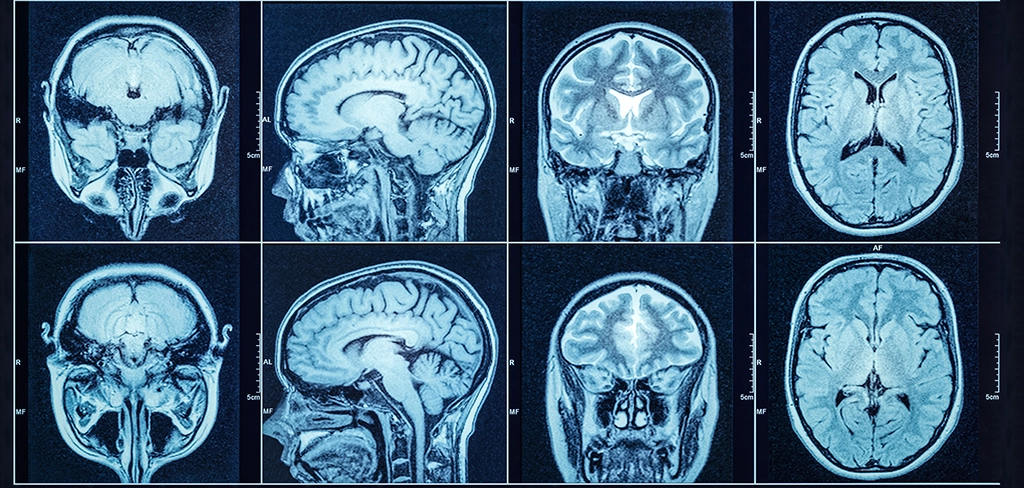

最后,对所有人群来说,在适当的情况下,推广使用替代成像方式:例如超声、磁共振成像(MRI)、或钼靶等。